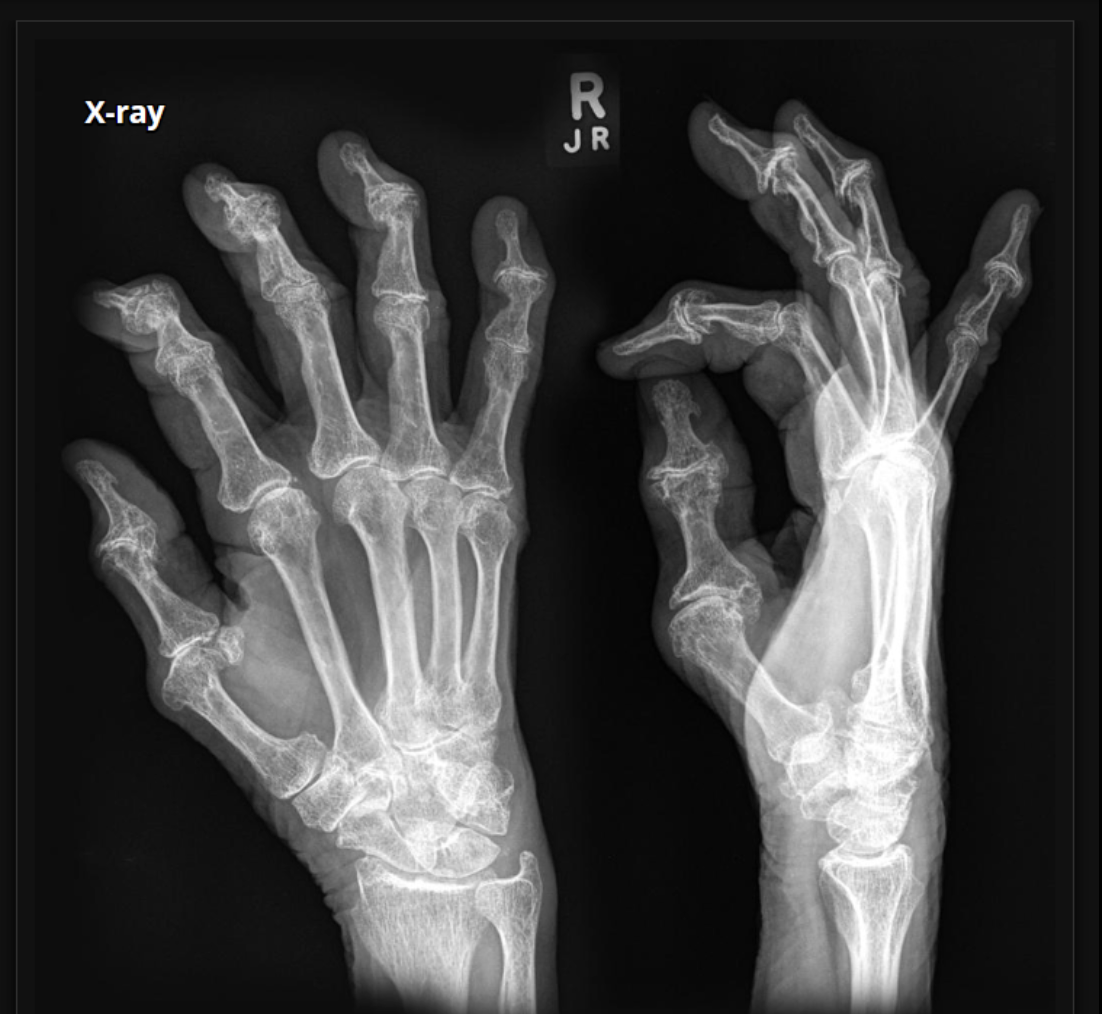

What pathological disease does this X-Ray show?

Rheumatoid Arthritis